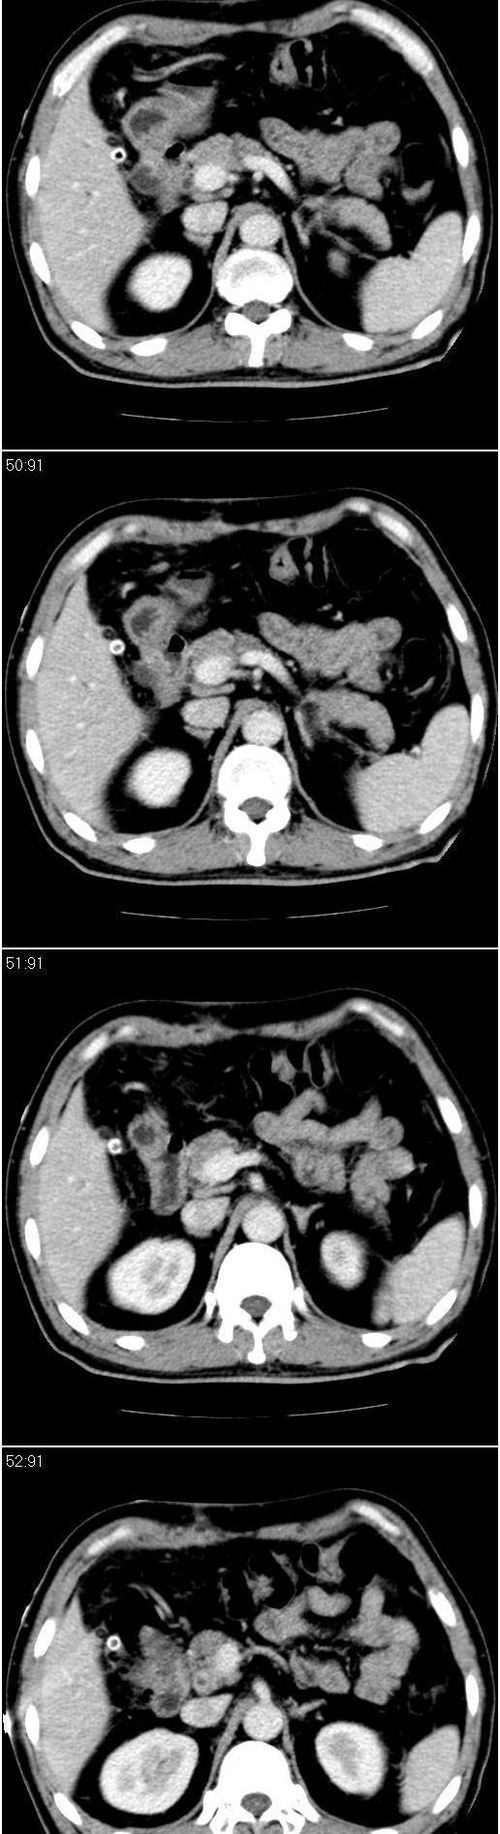

标题: CT13147:男,57岁。因胆结石阻塞性黄疸入院。 [打印本页]

标题: CT13147:男,57岁。因胆结石阻塞性黄疸入院。

男,57岁。因胆结石阻塞性黄疸入院。这是胆囊切除术后的照片,看看此片到底有什么问题。

肝内外胆管轻度扩张,胆囊窝内见引流管考虑胆囊切除术后改变.胃窦部软组织似增厚,建议胃镜检查.

现有资料很难说,薄层可能清楚些,如临床不提供,易诊断为术后改变。

肝内外胆管轻度扩张。楼主提示左右肝管合汇区域壁稍厚。胆总管末段壁似也稍厚有轻度强化。就现有资料诊断难。